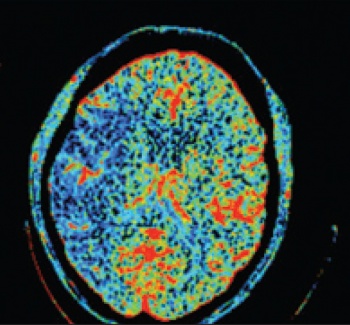

See Figures 1(i)-3(ii) for images of a successful endovascular therapy case.

Figure 1 (i): this and Figure 1(ii) show axial and coronal CT angiogram identifying proximal right MCA (M1) occlusion(click to enlarge)